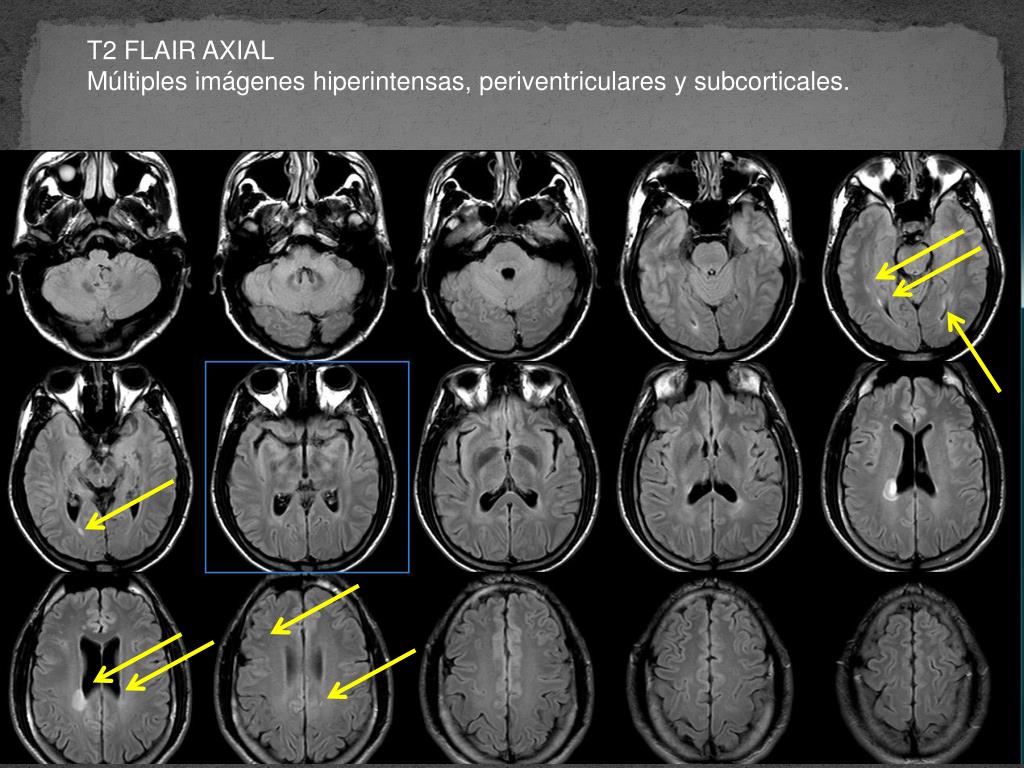

1. SesionStroke Caso clínico 12 de noviembre 2010 Dr. Arturo Violante Villanueva Neurólogo Torre Ángeles 822 Dr. Roger Carrillo Mezo Neurorradiólogo

14. T2 FLAIR AXIAL Múltiples imágenes hiperintensas, periventriculares y subcorticales.